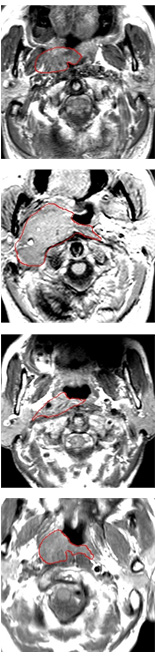

Currently, there is still no effort to fuse multi-modality MRI to develop an automatic segmentation system for NPC. According to researches of Popovtzer et al. [16], it should be a routine clinical practice to incorporate all kinds of MRI datasets in highly conformal radiation therapy to realize GTV delineation of NPC. For delineation of NPC, MRI is the perferred imaging modality for its superior soft tissue contrast [16, 3]. Moreover, MRI of different modalities data have different visual characteristics and various responses to different tissues and anatomical structures. For example, T1-weighted (T1) MRI is suitable for detecting skull base involvement and fat planes, while contrast-enhanced T1-weighted (CET1) MRI is used to identity tumor extent [3]. Figure 1 shows some examples of NPC response in T1, CET1 and T2-weighted (T2) MRI.

Refer to caption

Figure 1: Examples of slices from different MRI (T1, CET1 and T2), the contour of NPC is marked in red line. (a),(b) and (c) are slices from T1 , CET1 and T2 respectively.